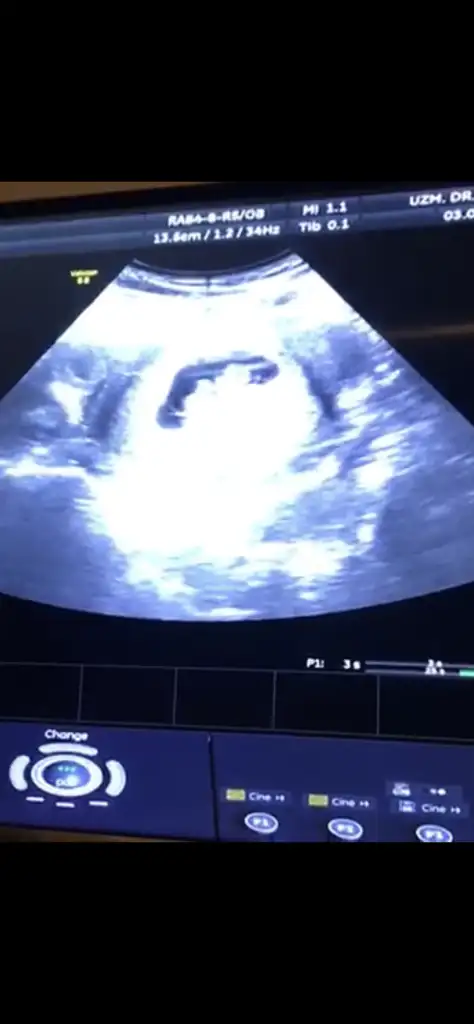

C425B453-5B1F-43F6-940F-BFE0834523C8.webp

Merhabalar herkes iyidir inşallah 🙏🏻 dün bir arkadaş kese şekli filan dye tahminde bulunuyordu hemen eksik kalmayayım dedm 😂 ben kız gibi hissediyorum ama ilk bebeğim olcak kızı da erkeği de istiyorum eşit oranda 🙈

kızda mı böyle oluyordu kesecik? 😇